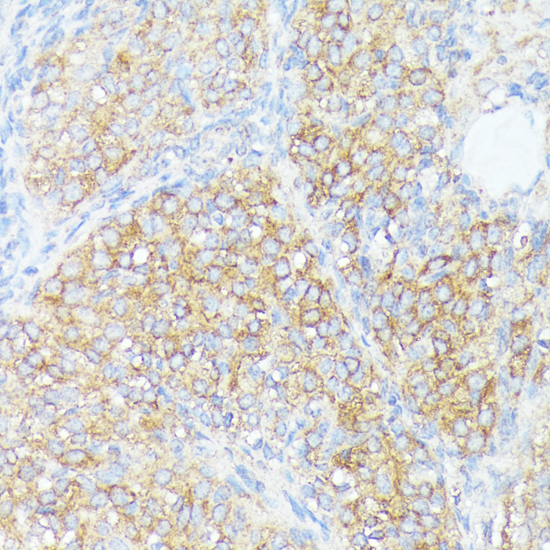

ApplicationWB, IHC: Recommended dilution: WB 1:500 - 1:1000, IHC-P 1:50 - 1:100